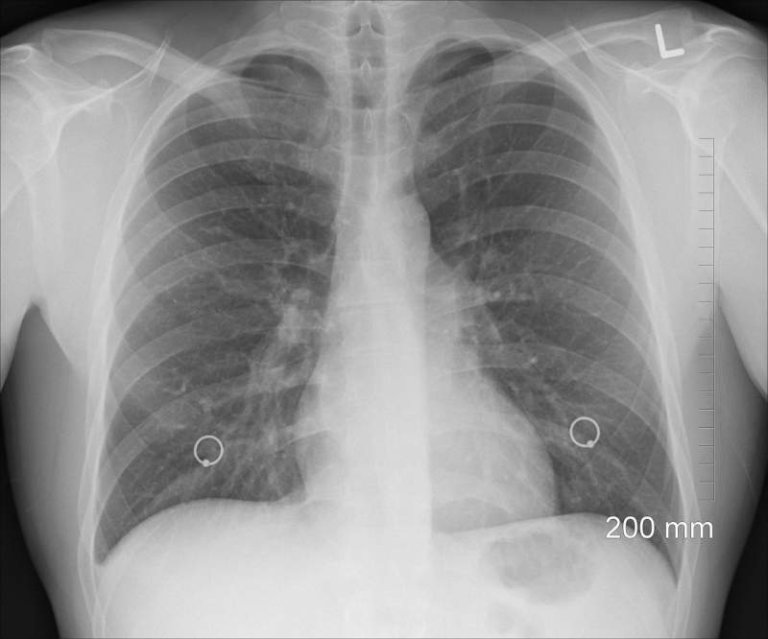

Top 10 Signs of Malignant Mesothelioma